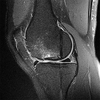

An 18-year-old man sustains a twisting injury to the left knee while playing football. An MRI scan is shown in Figure 48. What is the most likely diagnosis?

lateral mensicus tear

MRI scan shows a displaced, bucket-handle lateral meniscus tear. The sagittal view shows the typical “large anterior horn” sign, or “double meniscus” sign in which the displaced bucket-handle fragment appears just anterior to the native anterior horn of the lateral meniscus. The presence of the fibula on the sagittal view confirms this as the lateral compartment. The image is lateral and the cruciate ligaments are not visualized. The articular cartilage shown does not demonstrate an osteochondral lesion.